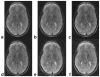

The correction of motion artifacts continues to be a significant problem in MRI. In the case of uncooperative patients, such as children, or patients who are unable to remain stationary, the accurate determination and correction of motion artifacts becomes a very important prerequisite for achieving good image quality. The application of conventional motion-correction strategies often produces inconsistencies in k-space data. As a result, significant residual artifacts can persist. In this work a formalism is introduced for parallel imaging in the presence of motion. The proposed method can improve overall image quality because it diminishes k-space inconsistencies by exploiting the complementary image encoding capacity of individual receiver coils. Specifically, an augmented version of an iterative SENSE reconstruction is used as a means of synthesizing the missing data in k-space. Motion is determined from low-resolution navigator images that are coregistered by an automatic registration routine. Navigator data can be derived from self-navigating k-space trajectories or in combination with other navigation schemes that estimate patient motion. This correction method is demonstrated by interleaved spiral images collected from volunteers. Conventional spiral scans and scans corrected with proposed techniques are shown, and the results illustrate the capacity of this new correction approach.